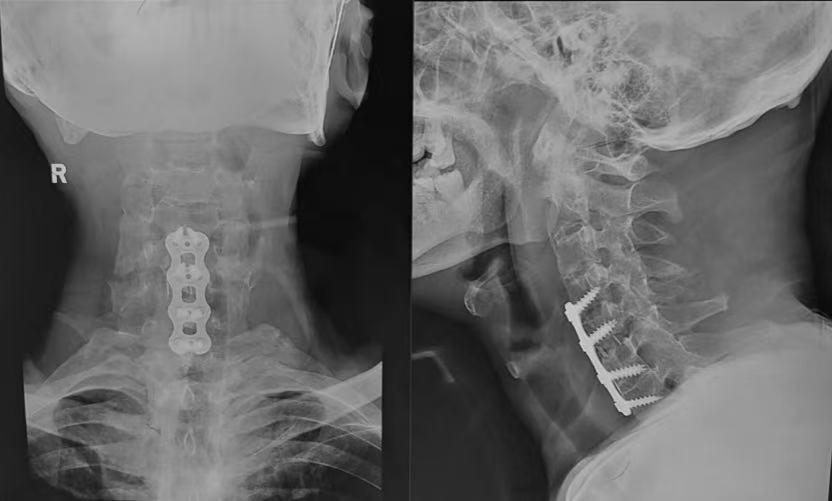

经过1个半小时的精心施术,随着最后一道缝合完成,手术宣告成功。手术室里紧张凝重的气氛,终于得以缓解。术后X光片显示,内固定位置准确,颈椎序列得到理想恢复。